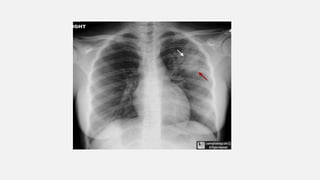

• #7  left upper lobe with fluffy, indistinct margins (red arrow) containing air bronchograms (white arrows). This was found to be a staphylococcal pneumonia.

• #9 n, Right Middle Lobe Mass. On the frontal image, there is a large mass in the right lower lung field. We note it is "silhouetting" the right heart border (red arrow) which is no longer seen as a distinct edge. It is not silhouetting the right hemidiaphragm (black arrow). The mass is therefore (1) touching the right heart border and is anterior and (2) the mass is soft tissue or fluid density. The lateral view shows the mass (M) is in the right middle lobe. It was a large bronchogenic carcinoma. n, Right Middle Lobe Mass. On the frontal image, there is a large mass in the right lower lung field. We note it is "silhouetting" the right heart border (red arrow) which is no longer seen as a distinct edge. It is not silhouetting the right hemidiaphragm (black arrow). The mass is therefore (1) touching the right heart border and is anterior and (2) the mass is soft tissue or fluid density. The lateral view shows the mass (M) is in the right middle lobe. It was a large bronchogenic carcinoma.